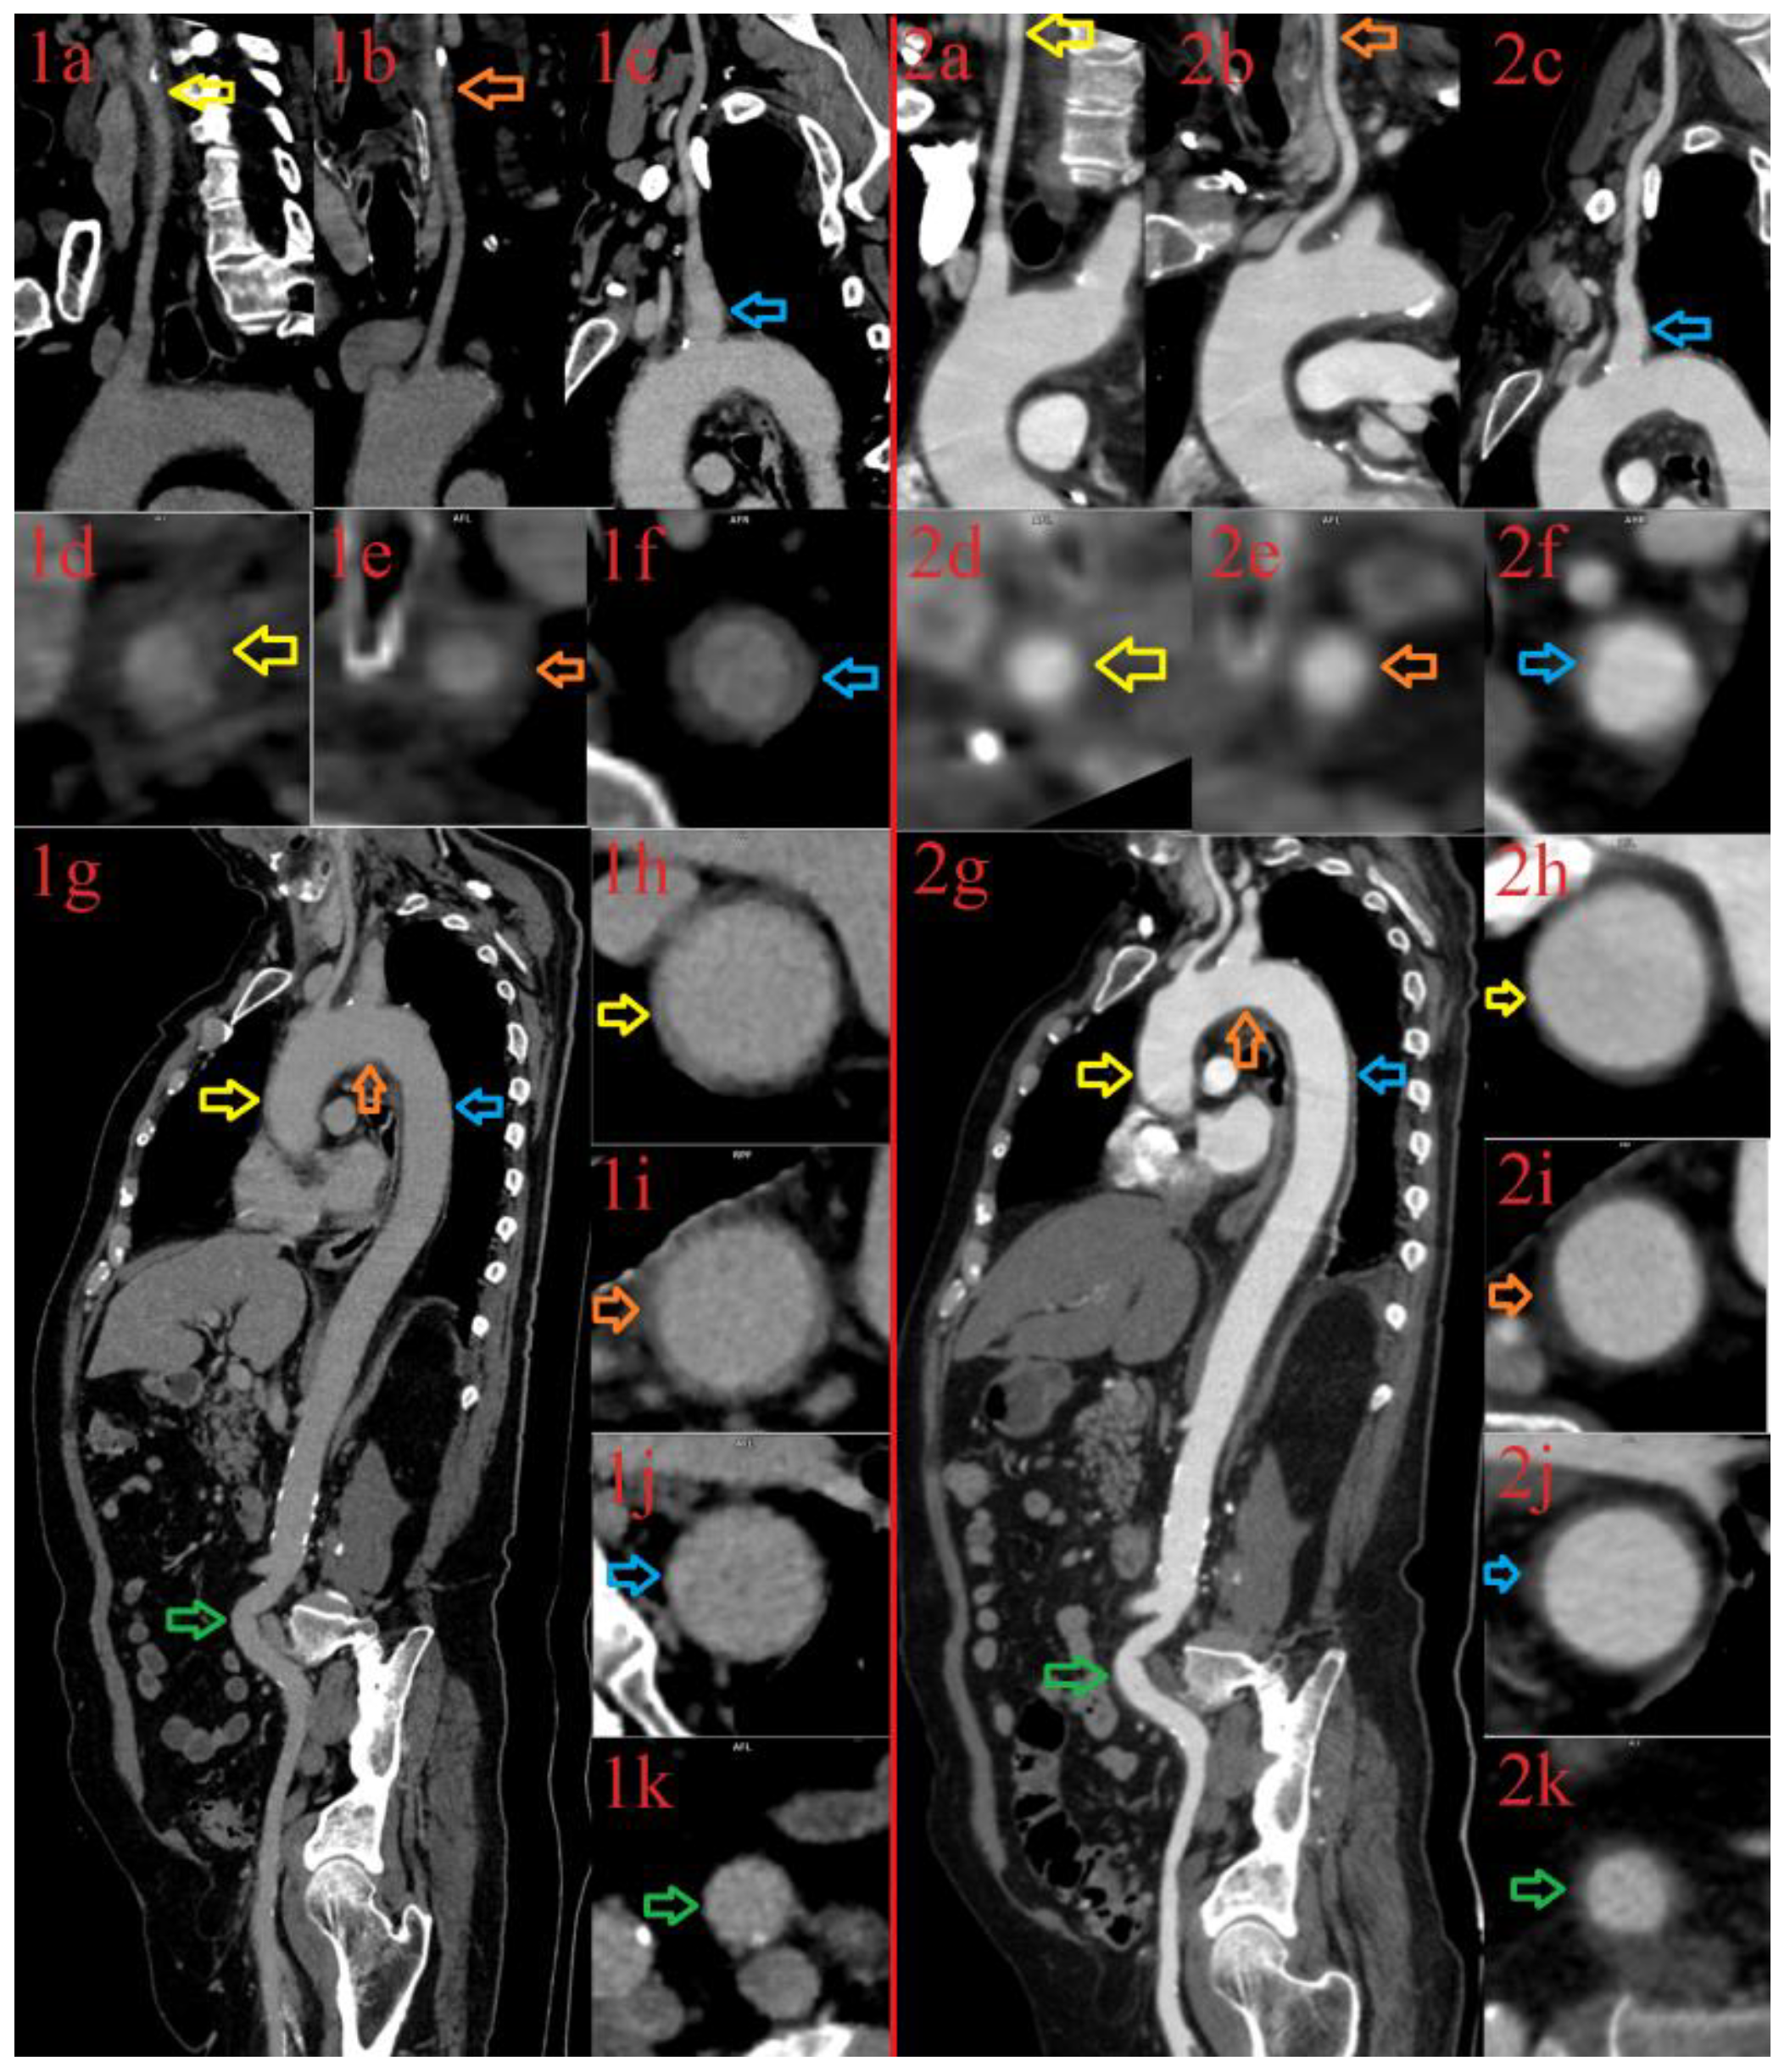

3.1.1. Patient 1

3.1.2. Patient 2